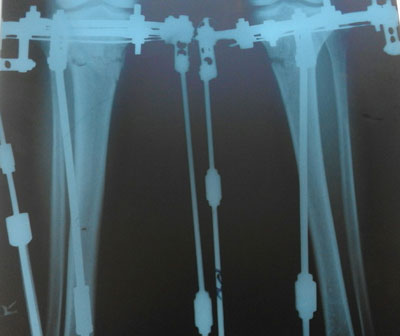

До круток.

На 4-ый день после операции.